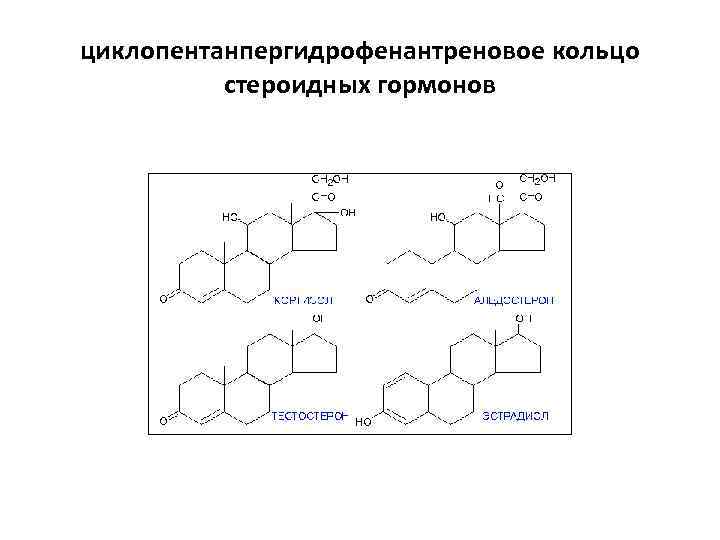

циклопентанпергидрофенантреновое кольцо стероидных гормонов

циклопентанпергидрофенантреновое кольцо стероидных гормонов

Стероиды характеризуются трехмерной пространственной конфигурацией, особенности которой оказывают существенное влияние на их биологическую активность.

Стероиды характеризуются трехмерной пространственной конфигурацией, особенности которой оказывают существенное влияние на их биологическую активность.